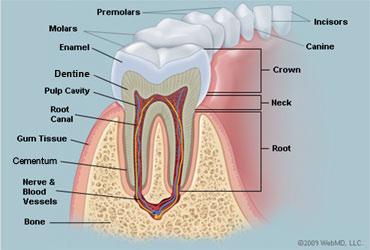

Crown

20

Neck

21

Root

22

Alveoli

23

Gingiva

24

Enamel

25

Dentin

26

Cementum